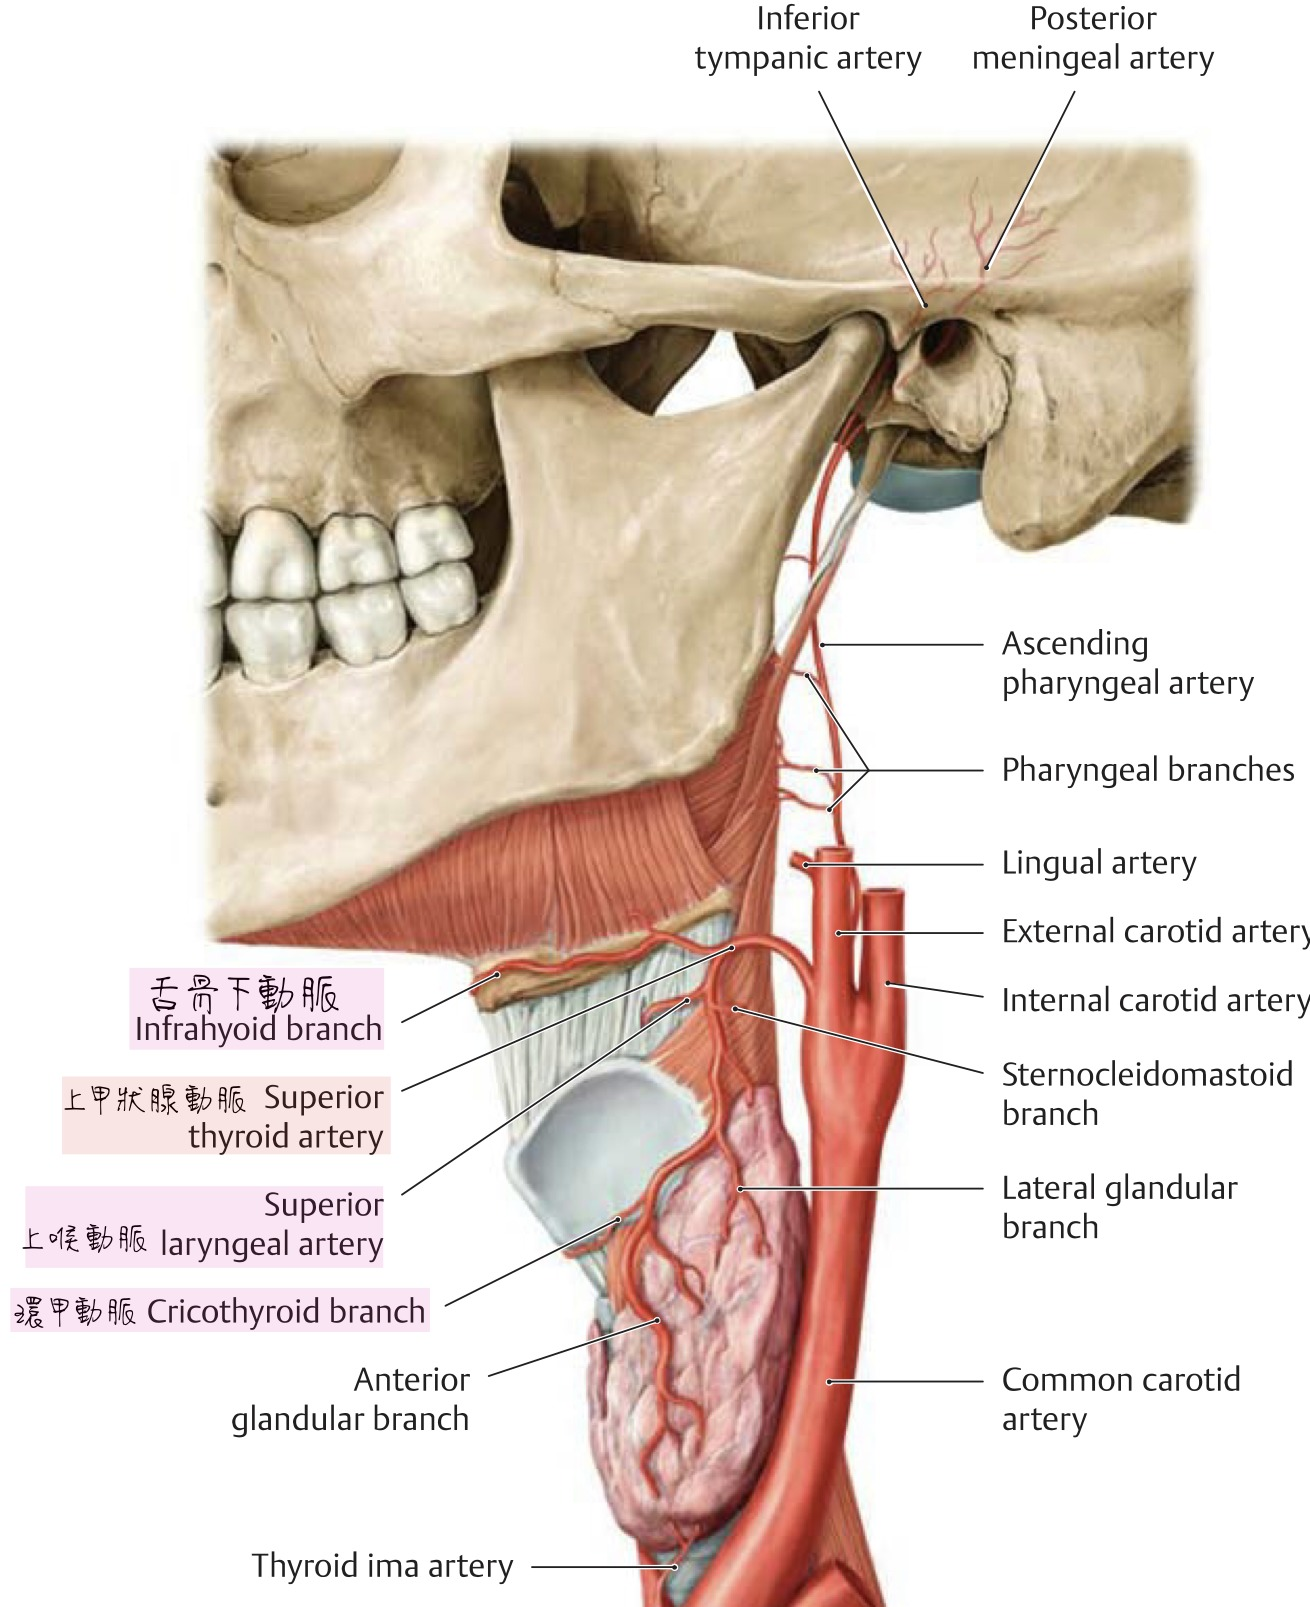

External carotid

- lingual a.

Superior thyroid artery

- Infrahyoid br.

- Sup. laryngeal a.

- SCM br.

- Cricothryoid br.

SCM血液

上1/3

中1/3

- Sup. thyroid a.

- Ext. carotid a.

下1/3

- suprascapular a. (>80%)

Internal carotid a.

- 進入carotid canal 前無分支